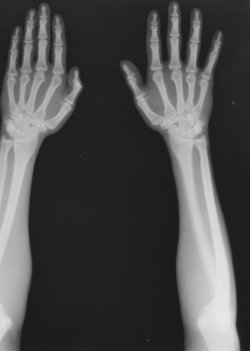

Christian Vogel analysiert das Erzeugen von „Epistemischem Sinn und ästhetischer Wirkung“. Sein Gegenstand ist die Entwicklung der Darbietungsformen von Röntgenbildern in Schaukästen im Prozess von Bildherstellung, Präsentation und Rezeption. Hier steht der Bezug auf einen ‚fotografischen‘ Realitätseffekt im Fokus.

Auch Vera Dünkel nimmt die Aufführungspraxis von Röntgenbildern „Zwischen Memento Mori und Spektakel“ in den Blick. Ihr Beispiel ist die Röntgencollage Ludwig Zehnders, einem Schüler Conrad Röntgens, mit dessen ideeller Orientierung an der zeitgenössischen Fotografie zum einen und an der medizinischen Bildtradition zum anderen.